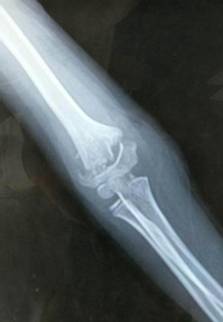

微创治疗肱骨干骨折

优点:闭合复位,不干扰骨折断端,中心固定,利于愈合。